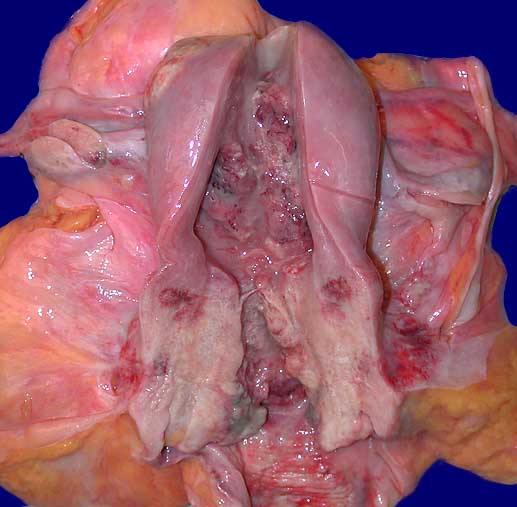

• Portio mit vorderer Muttermundslippe, Anteile der hinteren Muttermundslippe und Zervikalkanal.

• Carcinoma in situ der ektozervikalen Schleimhaut und des metaplastischen Plattenepithels im Bereich der Transitionalzone.

• Einwachsen des Carcinoma in situ in vorbestehende endozervikale Drüsenschläuche.

• Invasive solide Tumorzellstränge in desmoplastischem Stroma mit dichtem lymphoplasmazellulärem Entzündungsinfiltrat.

• Zellen des Plattenepithelkarzinoms mit vergrösserten, pleomorphen und hyperchromatischen Zellkernen, reichlich eosinophilem Zytoplasma und deutlichen Zellgrenzen.

• Zylinderepithel der endozervikalen Drüsen ohne Dysplasie. Das sollte der Kliniker dem Pathologen mitteilen: